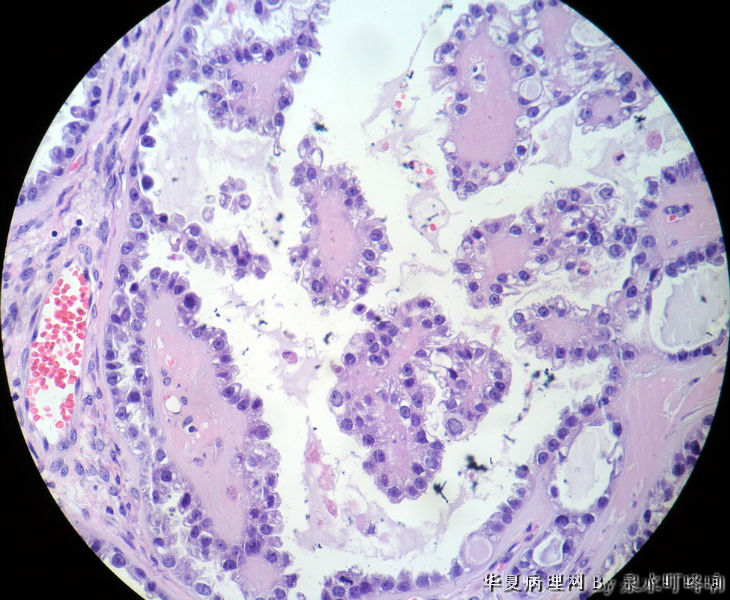

女,42岁,左卵巢肿物。

大体,灰褐色囊性肿物一个,大小约13×9×8厘米,临床已切开,内容物流失,肿物内壁可见多发乳头,最大4×3×3厘米,小者如绿豆大。

交界性乳头状浆液性囊腺瘤

倾向浆液性乳头状囊腺癌

交界性浆液性乳头状囊腺瘤

典型的透明细胞癌

透明细胞癌

间质玻变的乳头,鞋钉样细胞,腺囊状结构.....

经典的透明细胞癌。

考虑透明细胞癌,但有很多嗜酸性小体,需要排除变异型卵黄囊瘤。

天津肿瘤医院会诊:混合细胞上皮癌(透明细胞癌+浆液性囊腺瘤+勃勒那氏瘤)。